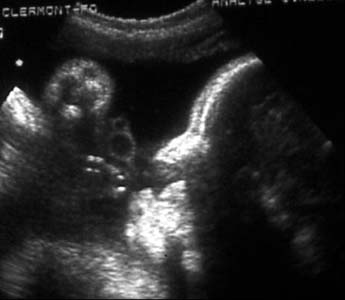

Anormalité de la ligne médiane